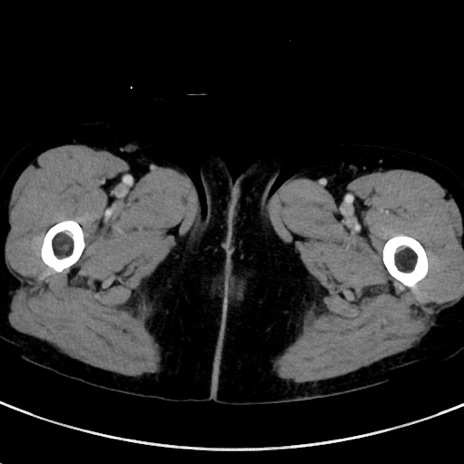

冠状断像